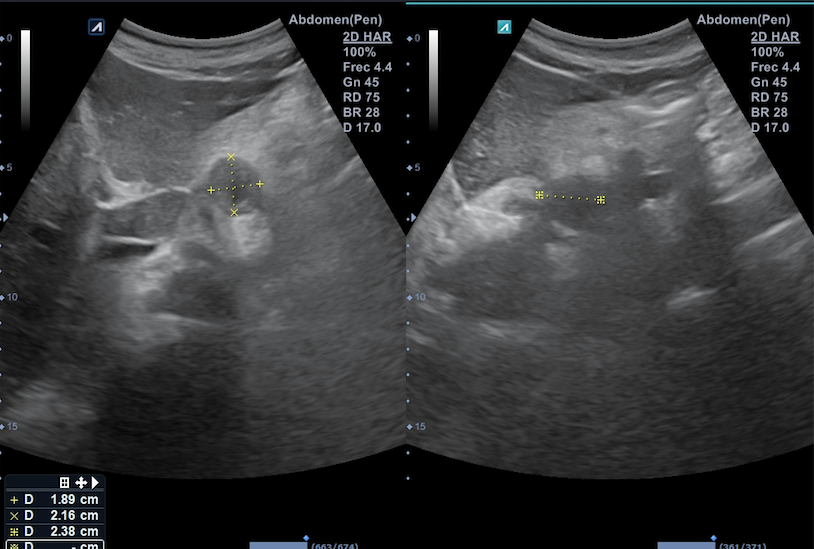

Citamos en consulta para realizar ecografía abdominal destacando a la exploración la presencia de 3 formaciones en retroperitoneo superior, en zona subdiafragmática y mediales al hiato aórtico: la primera a la derecha del tronco celiaco, de aspecto ovalado e isoecogénico de 1,2 x 1,9 cm; la segunda en línea media, debajo del lóbulo caudado, de aspecto hipoecogénico y con zona central de menor densidad de 1,9 x 2,2 cm; la tercera, a la izquierda de esta última de 2,2 x 2,8 cm sugerentes de adenopatías retroperitoneales.

El juicio clínico es adenocarcinoma gástrico y de esófago con afectación ganglionar, concordando las adenopatías retroperitoneales visualizadas en la ecografía con las adenopatías metastásicas en este caso.